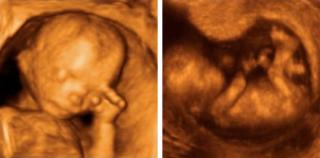

Un grupo de investigadores de las universidades Durham y Lancaster, en Reino Unido, revelaron que los niños en el vientre pueden sentir el estrés de sus madres, e incluso pueden expresar este malestar físicamente, moviendo su mano izquierda hacia el rostro.

Para realizar la investigación, los científicos británicos utilizaron ecografías en 4D, con las que observaron a 15 bebés y grabaron 342 ocasiones en las que se tocaron el rostro.

Las imágenes fueron captadas en cuatro etapas diferentes del embarazo, entre las semanas 24 y 36.

Fotografía: Madcapslaugh-Rizome (CC-BY-SA-3.0)